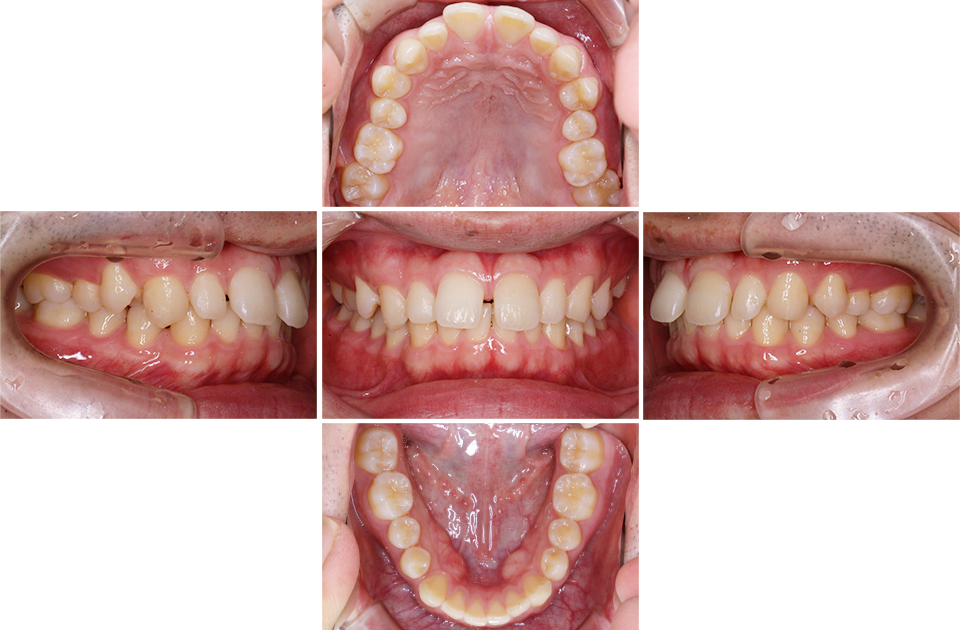

矯正後

矯正後 上顎

矯正後 下顎

主訴 正中が開いている。咬み合わせが深く歯肉を咬んでしまう。

年齢 20代

治療法 上下顎マルチブラケット装置

抜歯の有無 なし

治療期間 1年6ヶ月